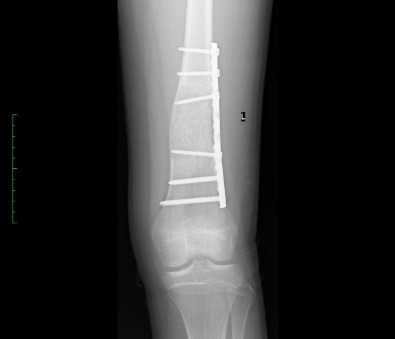

• Απλή ή Ανευρυσματική κύστη  στα οστά, παρουσιάζεται με παθολογικά κατάγματα (κατάγματα χωρίς να υπάρχει σοβαρός  τραυματισμός). Η απλή είτε η ανευρυσματική κύστη εάν προκαλεί συμπτώματα χρήζει χειρουργικής επέμβασης για αφαίρεση της.

Η εικόνα απεικονίζει περιστατικό με ανευρυσματική κύστη στο μηριαίο, το οποίο χειρουργήθηκε από τον Δρ. Ζένιο. Διενεργήθηκε  καθαρισμός της κύστης, τοποθέτηση μοσχεύματος και υλικό οστεοσύνθεσης.